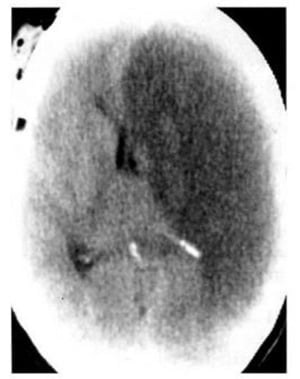

Hình 1.46. Khối máu tụ dưới màng cứng hỗn hợp cấp và mãn trong khối tụ bên trái. Mật độ cao trong khối lớn mật độ thấp tương ứng máu tươi bên trong một khối tụ máu mật độ thấp mãn tính.

Hình 1.47. Khối máu tụ bán cấp dưới màng cứng có mật độ ngang. Trước tiêm, chỉ thấy hiệu ứng choán chỗ và xóa mất não thất bên bên trái (a). Sau tiêm (b), các tĩnh mạch bề mặt hiện lên (mũi tên) cho thấy rõ hơn ranh giới của khối tụ máu.